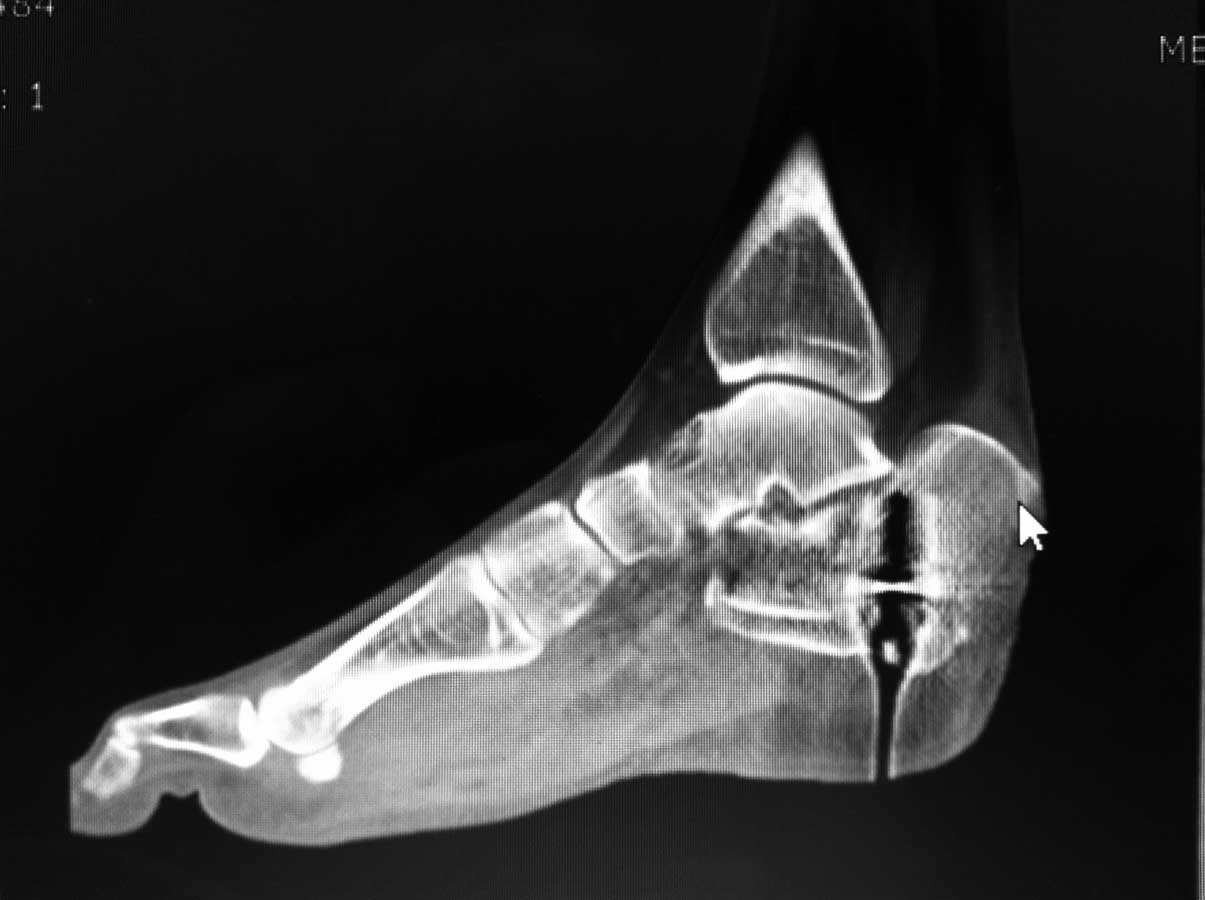

[Ortho] Перелом пяточной кости - ваше мнение?

немного КТ